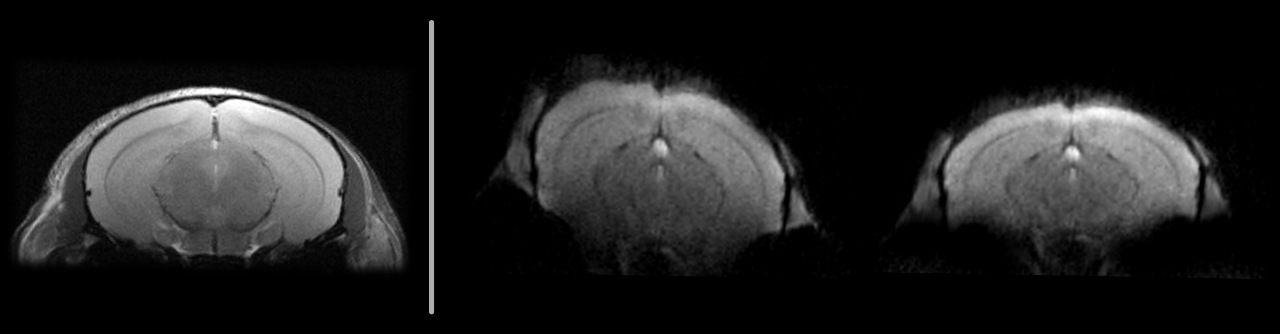

Single-shot EPI of in vivo mouse brain at 7T: original (middle) and field map-based corrected (right). Anatomical RARE reference (left).